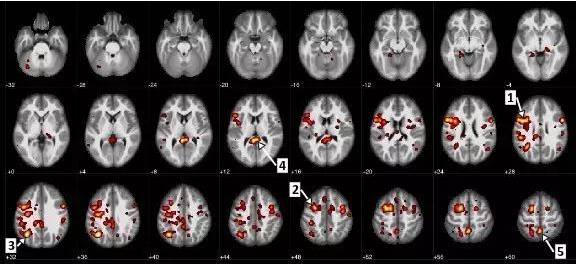

近日,IBM 科学家和阿尔伯塔大学加拿大埃德蒙顿分校在《自然》杂志的合作期刊《精神分裂症》(Schizophrenia) 上发布了新的数据,证明 AI 和机器学习算法能够以 74% 的准确率帮助预测精神分裂症病例。这项追溯性分析还表明,根据在大脑不同区域观察到的活动之间的关联,该技术能够从很高的相关性预测精神分裂症患者特定症状的严重程度。

这项开创性研究还可以帮助科学家识别更可靠、客观的神经影像生物指标 (Neuroimaging Biomarkers),用于预测精神分裂症及其严重等级。

在论文中,研究人员分析了来自开放数据集生物医学信息学功能研究网络 (fBIRN) 的去标识化的大脑功能核磁共振影像 (fMRI) 数据,数据中既包括精神分裂症患者和分裂情感性障碍患者,还包括健康的实验对照组。

fMRI 通过大脑特定区域的血流变化来测量大脑活动。具体来讲,fBIRN 数据集反映了,根据对调研参与者执行一个普通听觉测试时收集的数据,在不同清晰度水平上对大脑网络执行的研究。通过检查来自 95 位参与者的扫描影像,研究人员使用机器学习技术开发了一种精神分裂症模型,用于识别大脑中与该疾病相关的最紧密的连接。